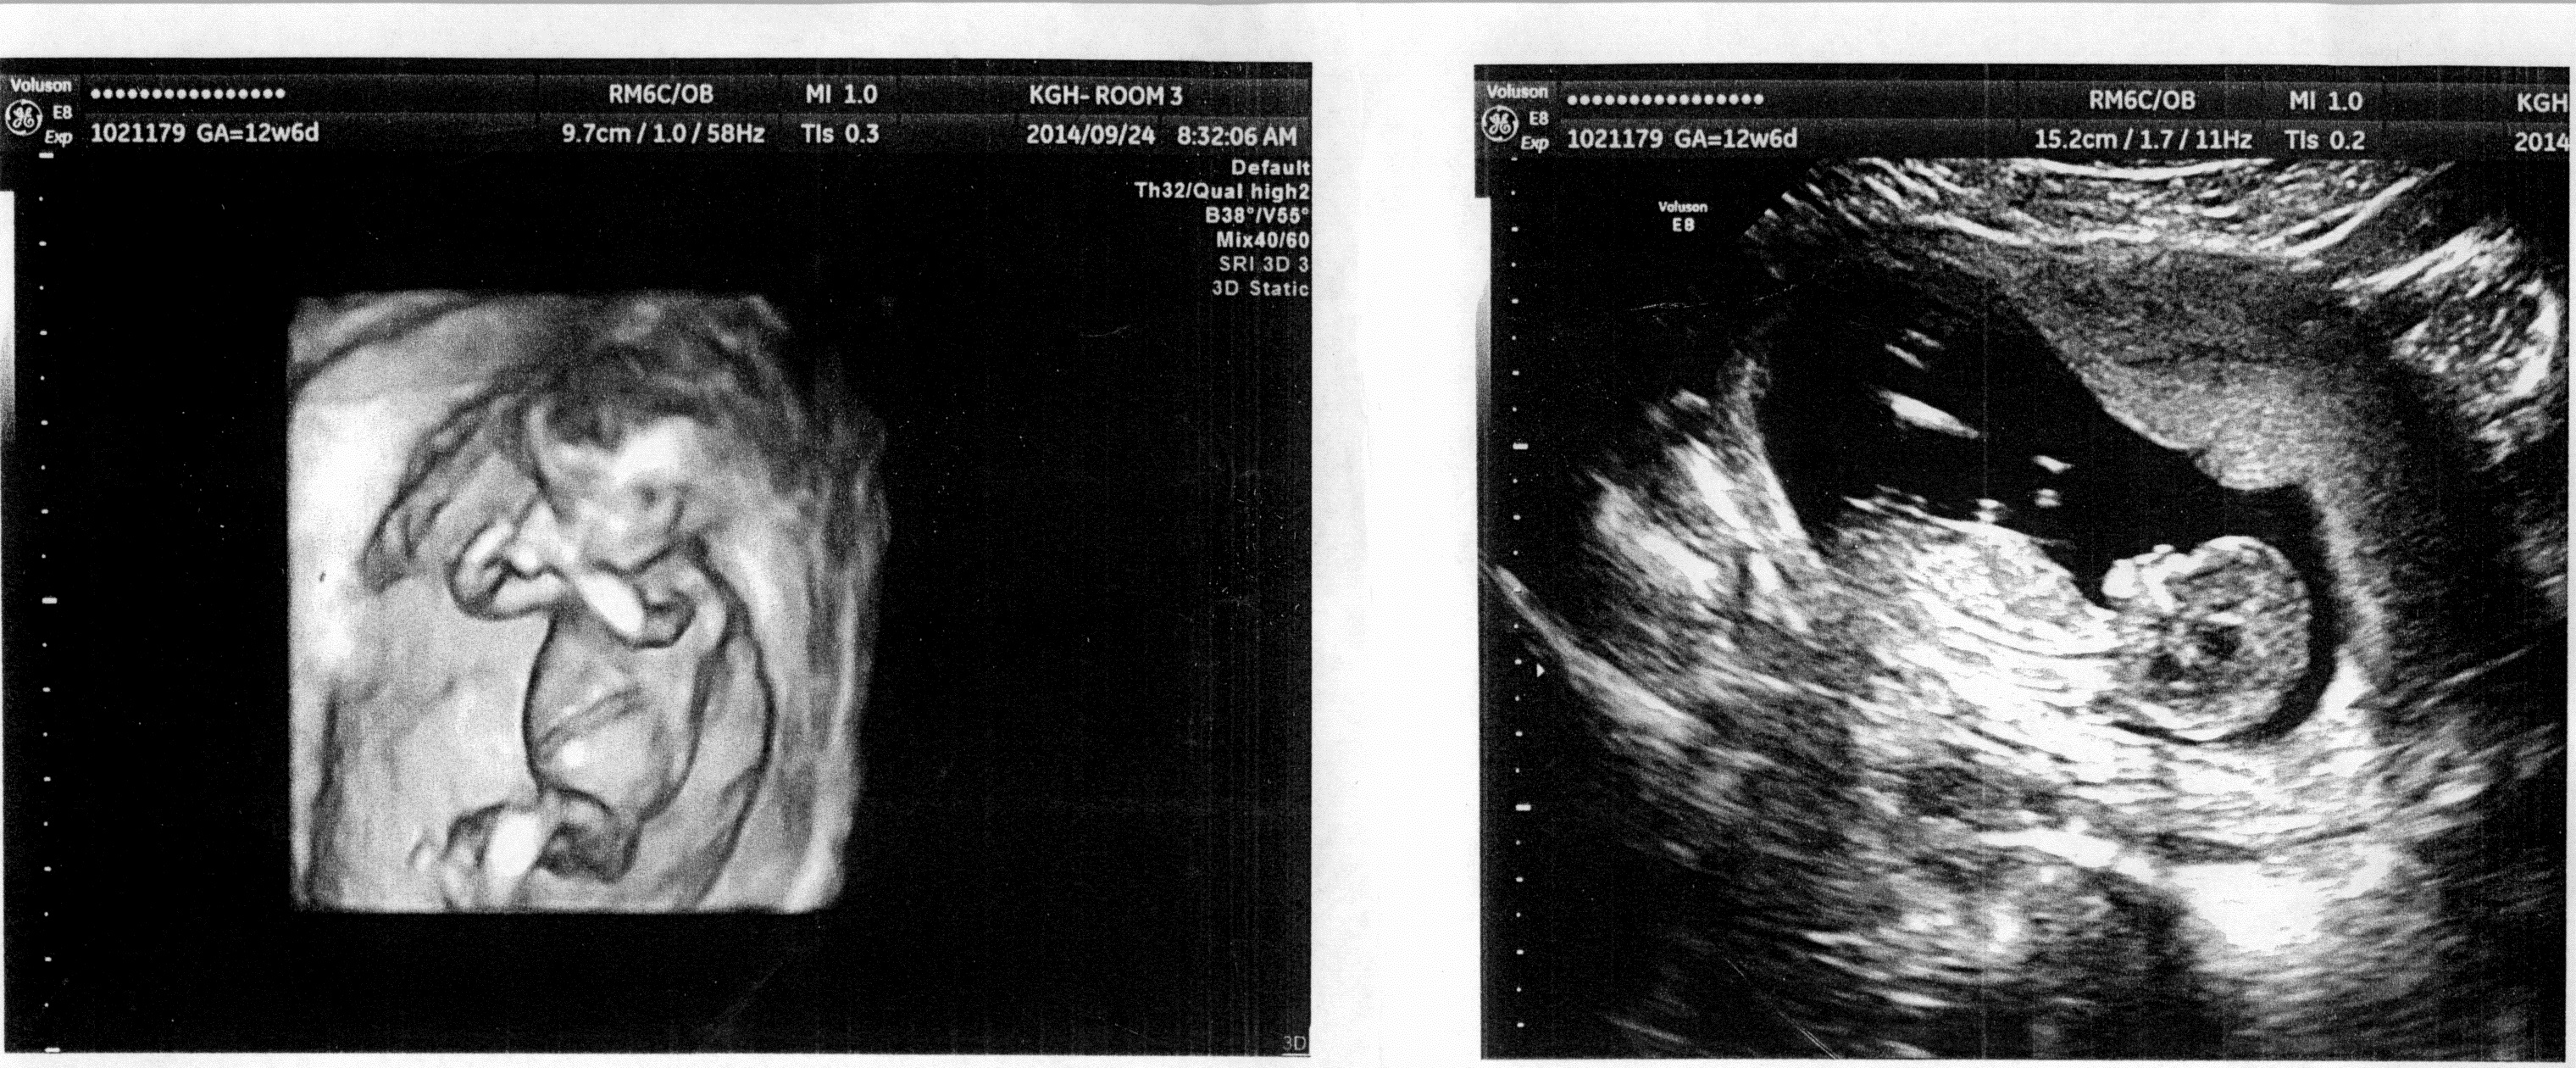

Attachment 21091 I hope I attached this properly!

Girl:)

girl based on 2nd image

Quote: Originally Posted by Finally5 based on skull? :) Second picture has a girly nub.